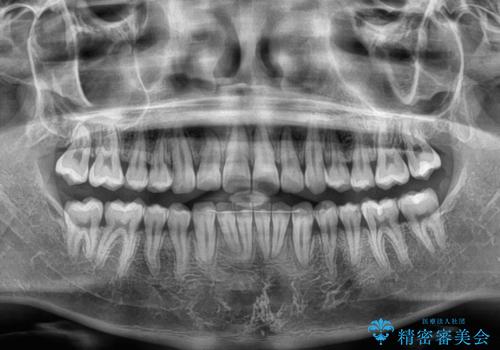

- ディープバイトと上顎前歯の突出、奥歯の咬み合わせを気にして来院された患者様です。

上顎歯列は全体的に前方位にあり、それが原因で深い咬み合わせとなり、突き上げにより上顎前歯が前方に飛び出している状態でした。

また、左右ともに上顎最後臼歯が頬側に転位している鋏状咬合となっていました。

インビザラインによる矯正治療をご希望でしたが、上顎歯列の前方位と鋏状咬合を確実に改善することを目的として、補助装置を併用することとしました。